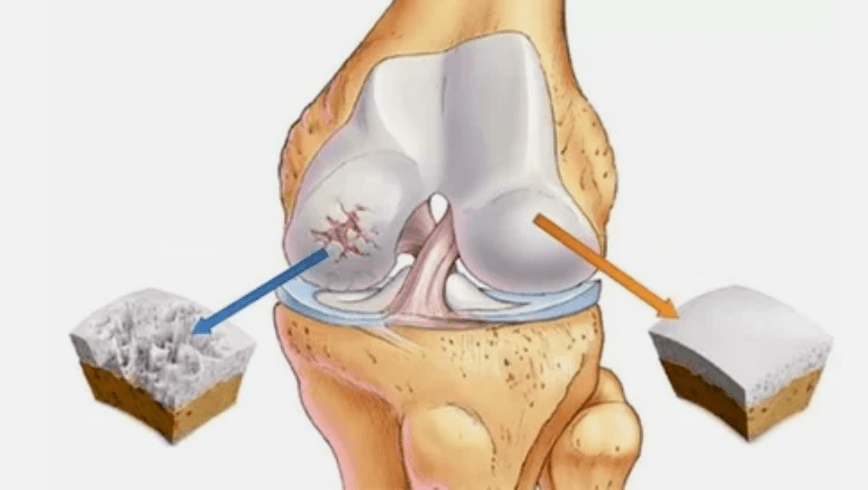

- Pathologies de revêtement Hyalin. L'amincissement du cartilage conduit au remplacement de ses tissus pathologiques - structures osseuses.

- Des croissances anormales apparaissent sur le cartilage - ostéophytes.

- La violation notamment de l'anatomie naturelle du cartilage et des os provoque la surcharge de zones saines du cartilage. La destruction des tissus articulaires sans traitement progresse constamment et entraîne un handicap.

Lorsque le degré de maladie augmente, les processus pathologiques sont encore aggravés. En fin de compte, tout le cartilage Hyalin est détruit.